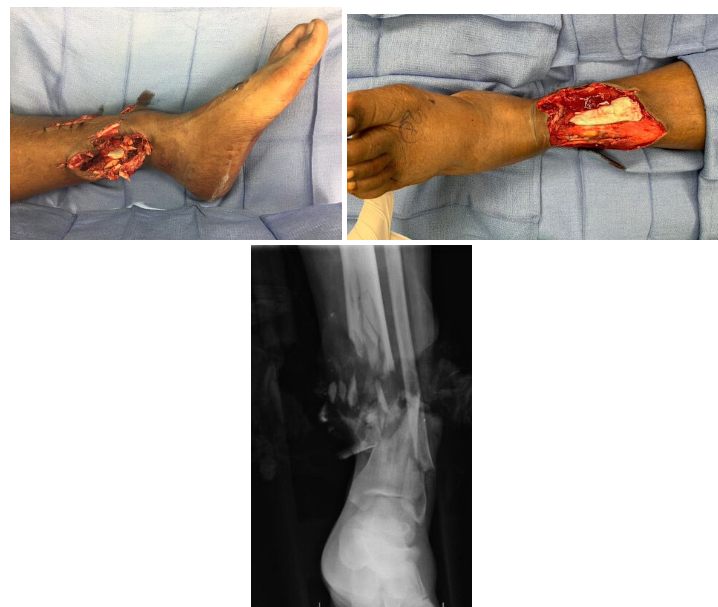

A 38-year-old man is brought to the emergency department after he sustained a Gustilo Type IIIB injury to the distal left lower extremity in a motor vehicle collision. Photographs and an x-ray are shown. A free flap is planned for soft-tissue coverage, and a temporary antibiotic bone cement spacer is placed in the 5-cm bone gap. Which of the following is the optimal time for using this induction membrane technique to perform the second- stage bone graft?

C. 6 weeks

The Masquelet technique (induction membrane technique) is an effective two-stage technique for managing large bone gaps (even greater than 20 cm). After appropriate debridement and soft-tissue coverage, the first stage involves meticulous debridement of the nonviable bone with placement of an antibiotic cement spacer to promote the creation of an organized pseudosynovial membrane rich in inductive molecules. During the second stage, the membrane is incised and cancellous bone graft is placed. The optimal time between the two stages is 4 weeks, but if delays are anticipated (especially with compromised vascularity or soft-tissues), the second stage can be performed at 6 to 8 weeks. The three largest published clinical series used 6 to 8 weeks for the second stage. At 1 to 2 weeks, the membrane has not formed adequately. Levels of growth factor release are lower before 4 weeks. After 4 weeks, the osteogenic capacity begins to decrease, so waiting 8 to 12 weeks has no advantage and may increase the risk for failure or nonunion.